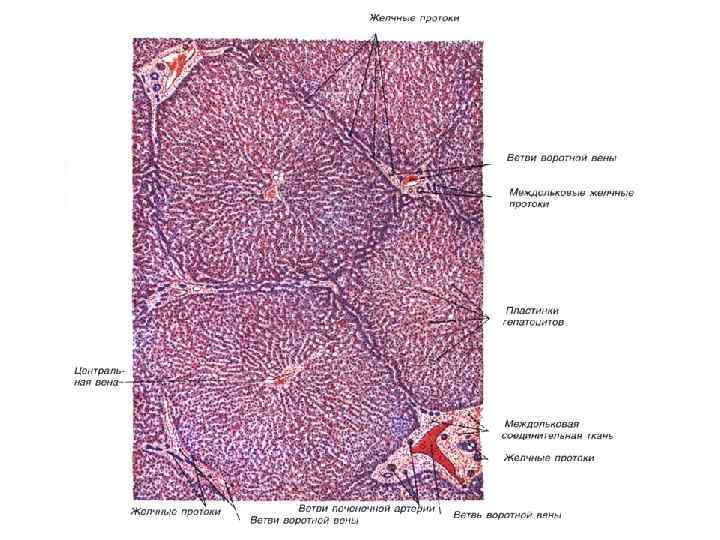

CV- центральная вена BD- желчные протоки * - синусоидные капилляры

1 - зона оптимального кровоснабжения, 2 - зона умеренного кровоснабжения, 3 - зона наихудшего кровоснабжения (наиболее уязвима при интоксикациях)

Препарат № 138 «Печень свиньи»

Триада печени

Препарат № 139 «Печень человека»

Препарат № 139 «Печень человека»

Препарат № 139 «Печень человека»

Триада печени

Печень человека. Окраска кармином (выявление сосудов)

Центральная вена и синусоидные капилляры